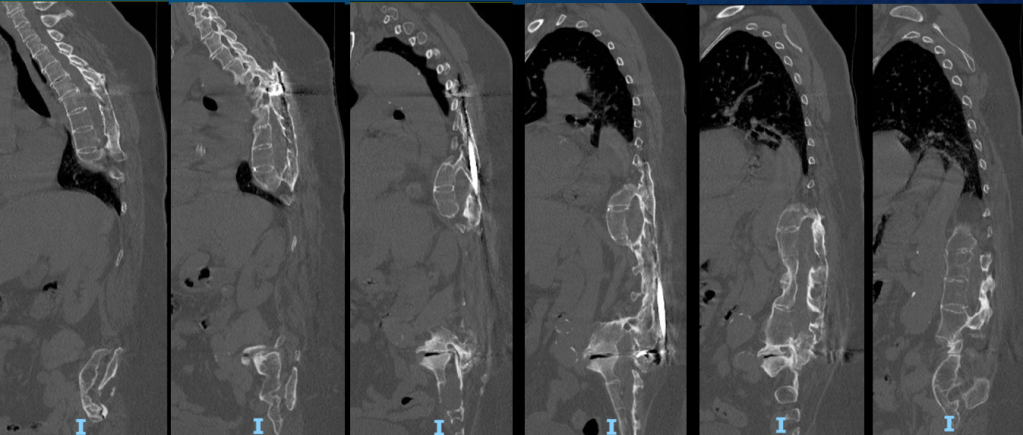

From robotics and AI-driven surgical planning to virtual modeling and custom implants, I’ve embraced a combination of tools that allow me to create tailored surgical plans for my patients—particularly those with scoliosis and spinal deformities.

What sets my approach apart is the seamless integration of these advanced technologies to ensure unparalleled accuracy and better outcomes for each patient.